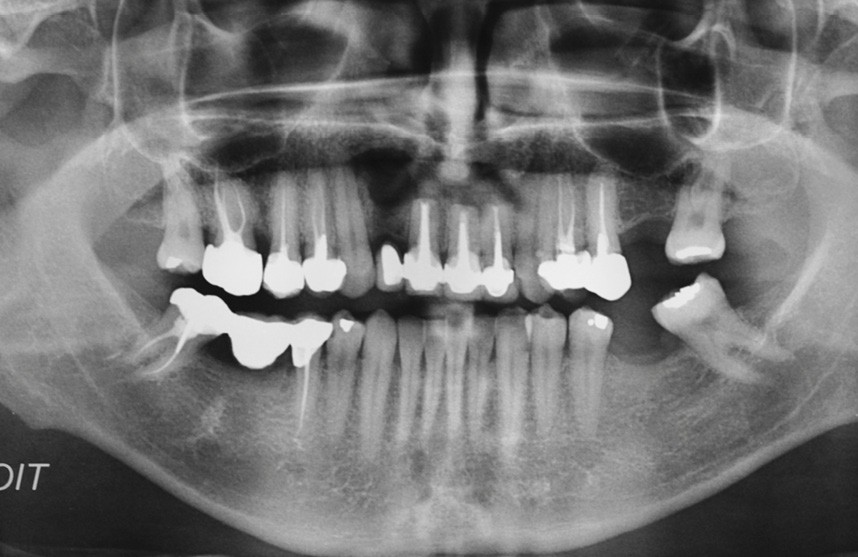

L’examen endobuccal montre deux fistules en regard des apex de 12 et 21 (fig. 1). Nous notons la présence d’une classe III squelettique, d’une occlusion inversée du côté droit (fig. 2) et des édentements non compensés au niveau de 26 et 36. L’orthopantomogramme révèle la présence d’une volumineuse lésion kystique qui s’étend de la 12 à la 22 (fig. 3).